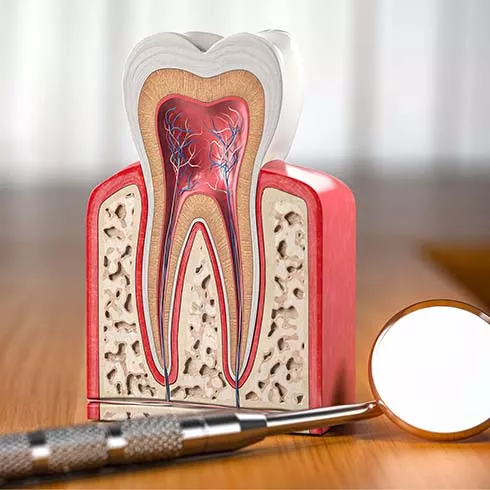

A damaged or cracked tooth can become infected, resulting in complications like severe toothache, an abscess forming above the tooth, or tooth loss. Damage to the tooth can result in bacteria entering the tooth and spreading, causing an infection of the soft tissues inside the tooth. This infection can spread into your gums and the bone surrounding the tooth's root. If left untreated, the infection can result in gum disease or the eventual loss of the tooth.

Root canal treatment involves the removal of the soft inner tissue of the tooth, also called the pulp. Your dentist will drill a tiny hole in the affected tooth and remove the pulp using special tools. After the pulp is removed, your dentist will clean the inside of the tooth to prevent further infection, fill the tooth with material, and seal the hole with a filling. After the procedure, your dentist will restore the tooth with a temporary dental crown while a permanent crown is being made.